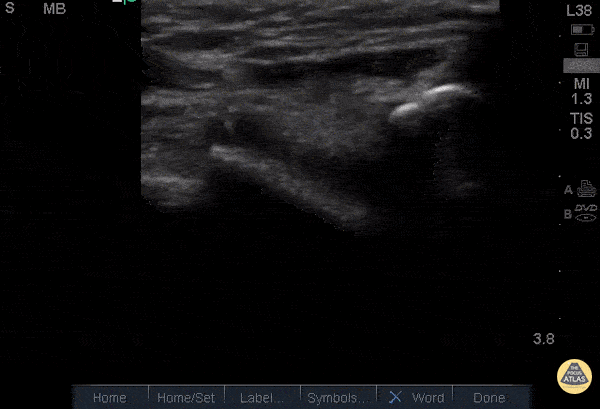

Musculoskeletal - Quad Tendon Rupture (Bilateral)

40 year old M presented with bilateral knee pain and inability to extend knees after injuring knee while carrying heavy plywood boards. POCUS confirmed the diagnosis of bilateral quadriceps tendon rupture. On ultrasound you can see the retracted tendon independent of the patella as the knee is being actively ranged. Also visible is a surrounding traumatic hematoma. One should look for discontinuity in the tendon in longitudinal view to diagnose any sort of tendon rupture. Often, there is an adjacent fluid collection reflecting hematoma. Be careful not to interpret the anisotropy of the ultrasound as discontinuity. Anisotropy is that the US looks different in cross section vs longitudinal views, any variation in the direction of the tendons and the positioning of the probe can lead to a false positive. Dr. Nathan Frank, Dr. Benjamin Weissman, Dr. Walter Valesky - Kings County/SUNY Downstate Emergency Medicine